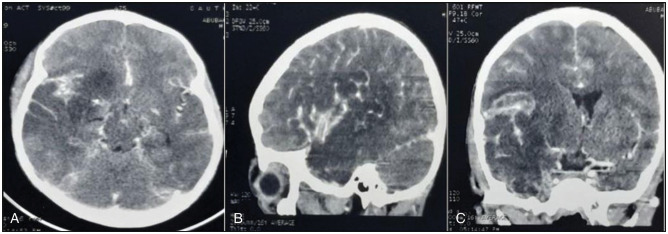

脑静脉窦血栓形成(CVST)是一种罕见且未被报道的神经系统疾病。这种情况有多种病因、临床表现,如果不及时治疗,会有明显的后遗症。我们报告的情况下,一个10岁的男性发烧,改变感觉,颅神经病变,和左偏瘫。他的影像学表现与CVST一致,随后入院时发现他的直肠有活蠕虫。他接受了非手术治疗,病情明显好转,出院时伴有残余运动障碍。此外,我们对已发表的CVST合并蛔虫病的病例报告进行了文献回顾,强调了其可能的病理生理、临床谱和管理特点。

Cerebral venous sinus thrombosis (CVST) is an uncommon and underreported neurological condition. This condition has varied aetiologies, clinical manifestations, and significant sequelae if left untreated. We report the case of a 10-year-old male with fever, altered sensorium, cranial nerve neuropathies, and left hemiplegia. His imaging findings revealed features consistent with CVST, and he was subsequently noticed to be passing live worms per rectum while on admission. He was managed nonoperatively, improved significantly, and was discharged with residual motor deficits. In addition, we present a literature review of published case reports of CVST associated with helminthiasis, highlighting its possible pathophysiology, clinical spectrum, and management peculiarities.